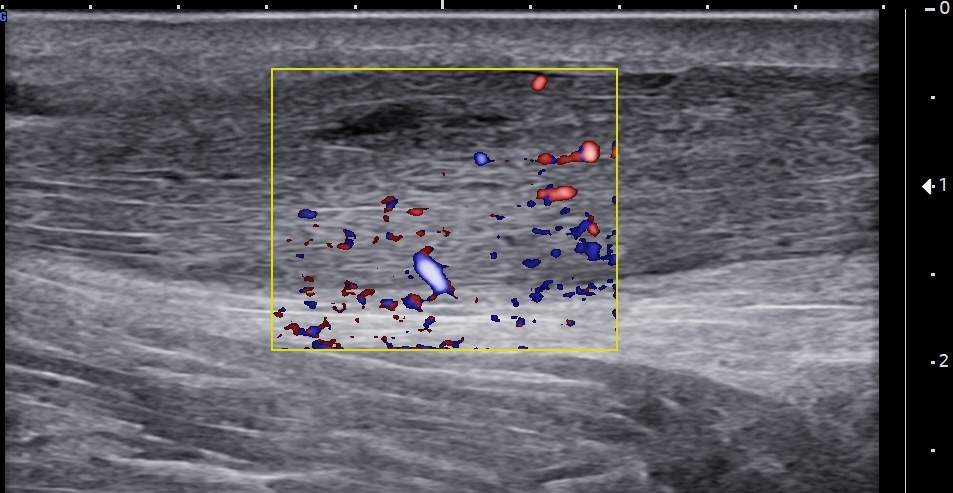

Unlabeled short-axis ultrasound image of the midportion Achilles tendon using color Doppler, demonstrating multiple intratendinous neovessels consistent with chronic and severe tendinopathy.